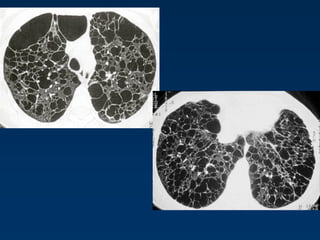

Langerhans Cell Histiocytosis

HRCT Findings

Small peribronchiolar nodules (1-5mm)

Thin-walled cysts (< 1cm),

Bizarre and confluent

Ground glass opacities

Late signs: irreversible / parenchymal fibrosis

Honey comb lung, septal thickening,

bronchiectasis

1 year later

Peribronchiolar Nodules Cavitating nodules and cysts

Langerhans Cell Histiozytosis

Key Features

Upper lobe predominance

Combination of cysts and noduli

Characteristic stages

Increased Lung volume

Sparing of costophrenic angle